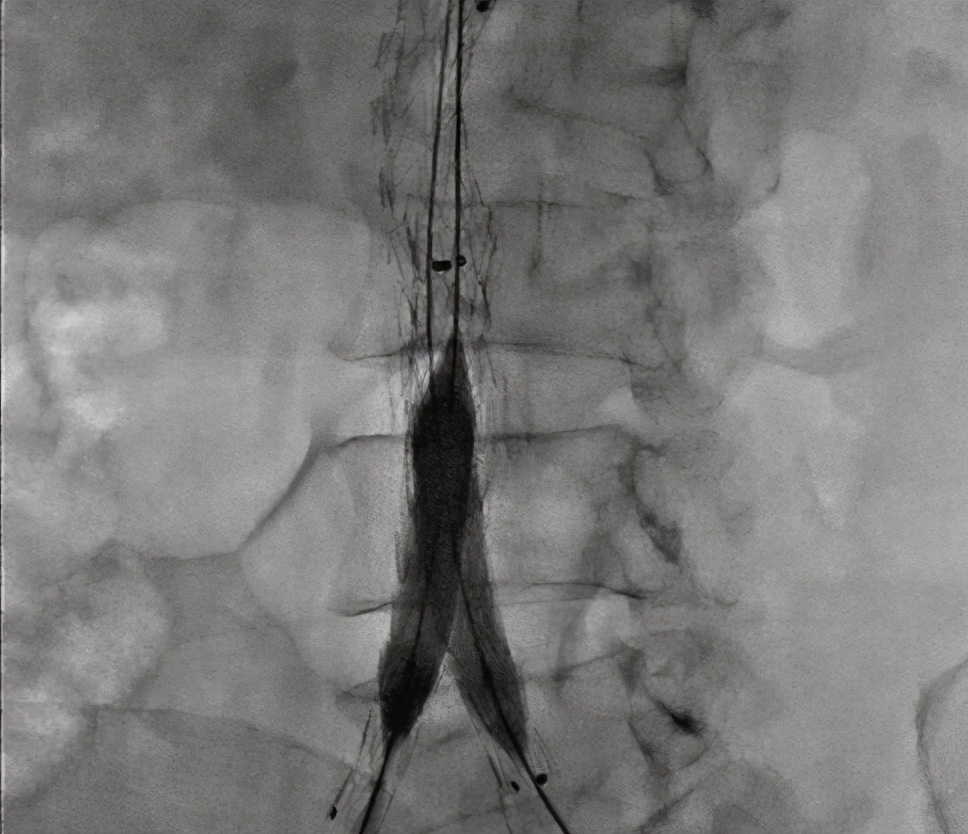

④主动脉造影

典型的小叶囊性动脉瘤,通常为多发或连续型。主动脉壁有无动脉硬化。因为覆盖了血栓或周围策划,血栓可能是不规则的,当血栓充满肿瘤腔时不能形成。